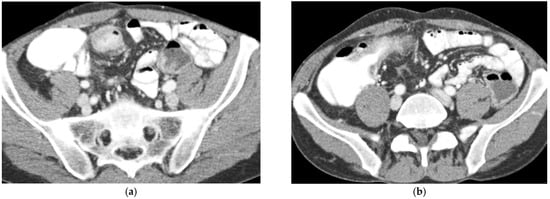

T2-weighted sequences (Figure 1a–c) are fundamental for a comprehensive morphological assessment of Crohn’s disease on both axial and coronal planes. They allow accurate definition of disease location, longitudinal extent, and severity, including evaluation of bowel wall thickening, luminal narrowing, and the presence of penetrating complications such as fistulas and abscesses at any level of the small and large bowel. These sequences are also essential for assessing extraintestinal manifestations of disease, including inflammatory changes of the surrounding mesenteric fat. Beyond structural assessment, T2-weighted imaging plays a pivotal role in the detection of inflammatory activity through the identification of mural and mesenteric oedema. In particular, Fat-Suppressed T2-weighted sequences enhance the conspicuity of oedematous tissue with a higher T2-signal, and currently represent the only imaging technique capable of directly demonstrating oedema at the level of the intestinal wall, mesenteric lymph nodes, and mesentery. Oedema is the hallmark of active inflammation, reflecting increased vascular permeability and interstitial fluid accumulation [6,12,13,14,15,16]. As such, it provides information that is complementary to mural hypervascularization observed on contrast-enhanced sequences, contributing to a more integrated and comprehensive assessment of disease activity [15,16]. Pre- and post-gadolinium–enhanced T1-weighted sequences enable detailed assessment of mucosal and transmural enhancement patterns (Figure 1d–g), which reflect bowel wall vascularity and the degree of inflammatory activity. These sequences are essential for evaluating not only the affected bowel segments, but also associated inflammatory changes in the mesentery and regional lymph nodes.

Figure 1.

20-year-old female patient with typical Crohn’s disease of the terminal ileum, evaluated with a 3T Magnet, following oral ingestion of 1500 cc of PEG solution. (a): Coronal T2w images obtained with breath-hold acquisitions show diffuse inflammatory thickening of the last ileal loop exceeding 15 cm in length. Note how the remaining loops of the small bowel wall appear normal in contrast with the affected ileal loop. (b,c): axial T2 w images showing pathological thickening of the last ileal loop. (d,e): coronal T1-weighted scan after gadolinium injection, showing marked enhancement of the ileocecal valve and terminal ileum wall. In particular, an increased mucosa enhancement is clearly visible in the terminal ileum, well distinguishable from the normal mucosa of the remaining ileal and jejunal loops. The terminal ileum is affected for at least 15–20 cm; local mesenteric hyperaemia is also observed. The entire small bowel is fully displayed (d), including jejunal and ileal loops, which appear normal with respect to the affected terminal ileum. (f,g): Axial Gd-enhanced T1-weighted images show marked concentric wall thickening and enhancement of the terminal ileum with associated mesenteric hyperaemia, due to severe inflammatory involvement. (h): Post-processing “fusion” image, in which the T2 image is merged with the post-contrast T1 image, highlighting the pathological ileal loop in 20-year-old female patient with Crohn’s disease.

In addition, dynamic assessment of Gd-enhancement over time provides clinically relevant information in patients with Crohn’s disease. In the setting of active inflammatory disease, affected bowel segments typically demonstrate early and intense mural enhancement during the arterial phase, approximately 20 to 30 s after intravenous contrast administration, reflecting hyperemia and increased vascular permeability. Conversely, in predominantly fibrotic (fibrostenotic) disease, Gd-enhancement tends to be more gradual and progressive, with peak mural enhancement observed in the delayed phases, approximately 3–7 min after contrast injection. This delayed pattern is consistent with reduced vascularity and a greater proportion of fibrotic tissue within the bowel wall [17,18,19].

This combination of structural and functional information makes MRE particularly powerful in assessing CD inflammatory activity. Increased mural thickness, hyperintensity on T2-weighted imaging, layered or transmural enhancement after contrast administration and restricted diffusion are features that correlate closely with endoscopic markers of disease severity [6,7,8,9,10,11,12,13,14,15,16,17,18,19,20]. Indeed, these imaging markers form the basis of validated scores such as the Magnetic Resonance Index of Activity (MaRIA), which is now widely accepted as a reliable surrogate for mucosal inflammation in both the ileum and colon [11,12,13,17,19,20,21]. CD activity MRI features can be further enhanced using Fusion Imaging and post-processing techniques, which can synthesize and highlight Gd-enhancement, T2-weighted and DWI at the level of the affected bowel loops (Figure 1h and Figure 2c).

Figure 2.

47-year-old female patient with recurrent ileal Crohn’s disease following resection. (a) Coronal T2-weighted image demonstrating recurrent ileal Crohn’s disease at the anastomotic site, characterized by marked bowel wall oedema. (b) Corresponding axial T1-weighted image after gadolinium administration showing intense mural hyperenhancement of the affected ileal loop. (c) Post-processed color-coded map derived from the T1-weighted gadolinium-enhanced sequence, with areas of maximal enhancement highlighted in red. (d) Single-shot fast spin-echo sequence with follow-through–like appearance, clearly depicting the lumen of both normal and pathological small-bowel loops. (e) Axial diffusion-weighted imaging (DWI) showing marked diffusion restriction within the diseased ileal segment.